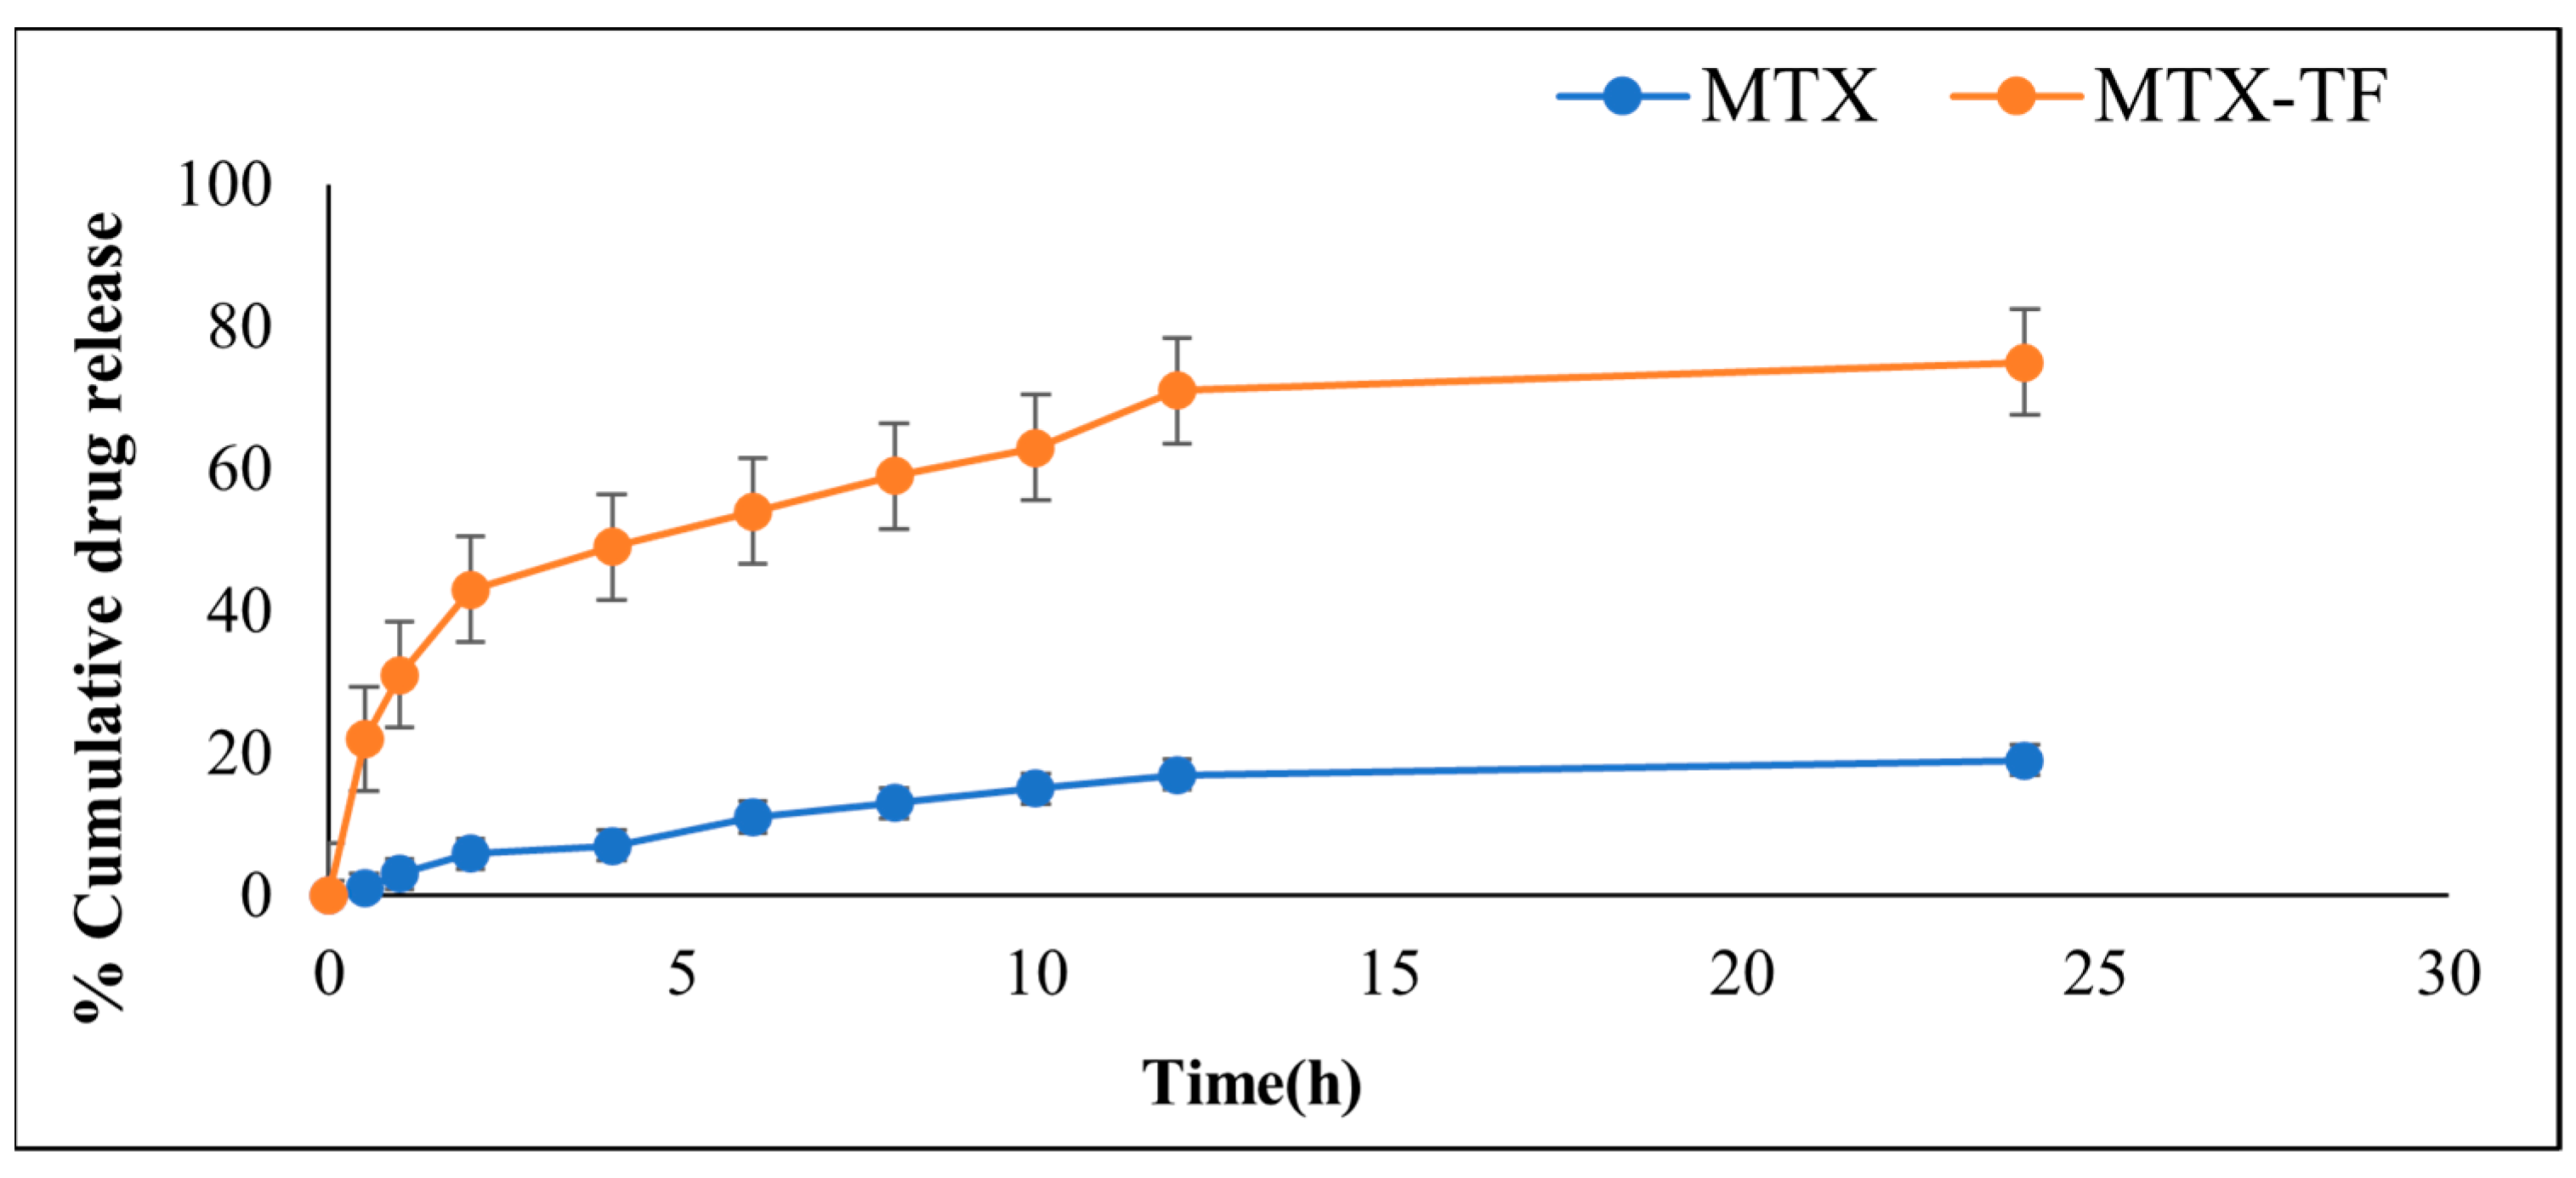

2.5.2. In Vitro Drug Release

2.6.3. In Vitro Release Study of MTX-MN and MTX-TF-MN

3.2.7. In Vitro Drug Release

3.4.3. In Vitro Release Assay for MTX-MN and MTXTF-MN